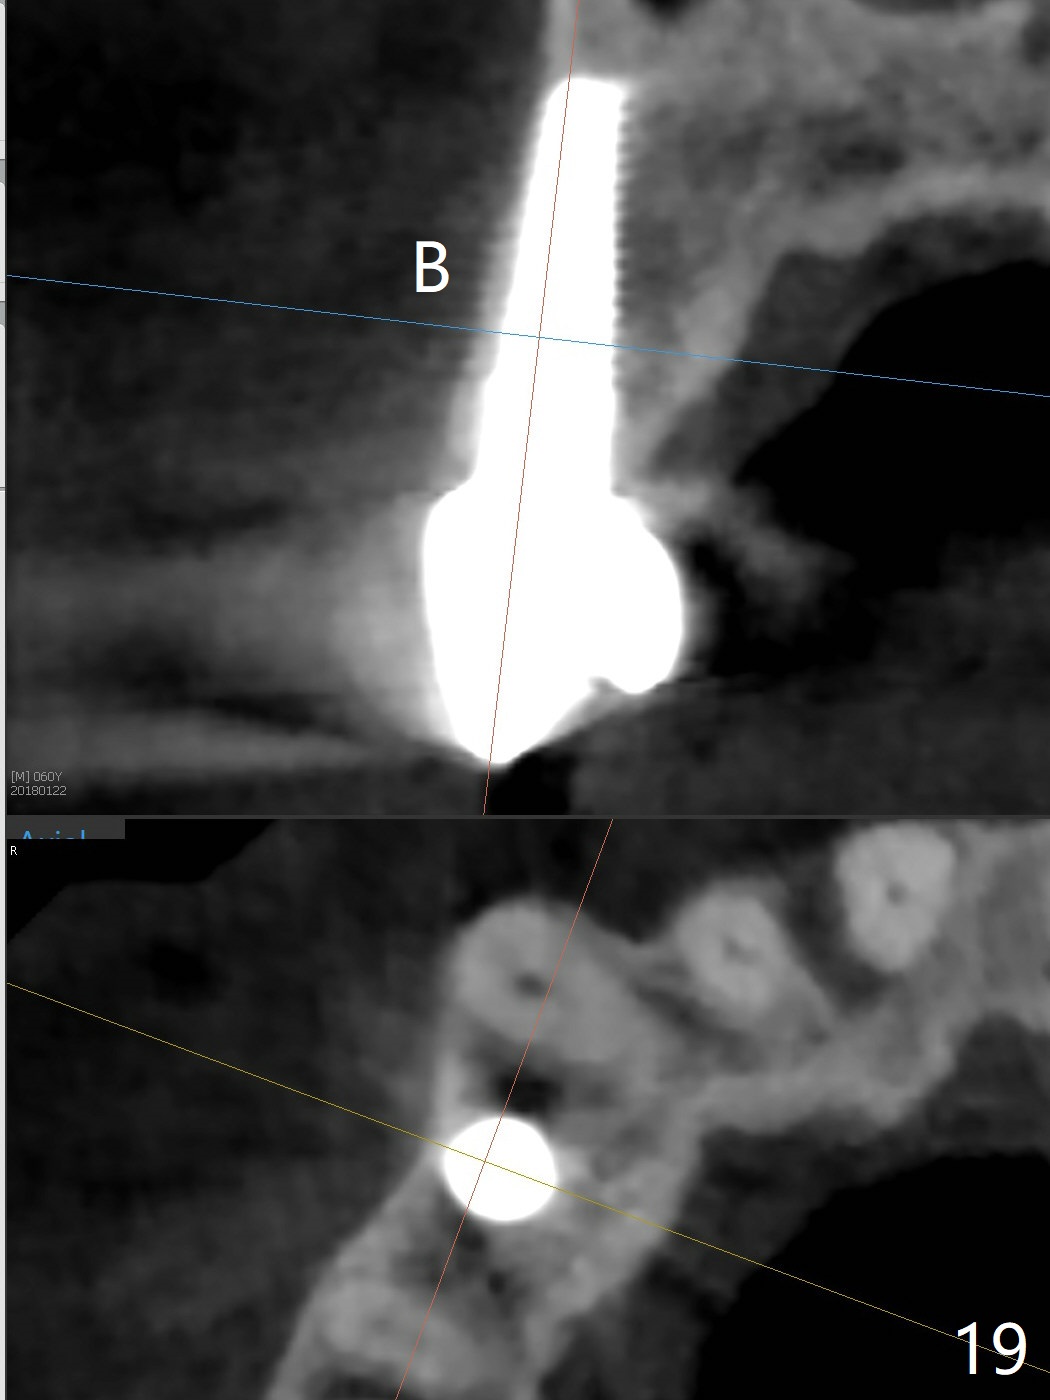

The long implant seems to be appropriate for the patient with periodontitis and bruxism (Fig.18, 2 years, 10 months post cementation). The implant appears to be placed buccally (B, Fig.19,20 (CBCT coronal and axial sections), 4 years, 5 months post cementation).